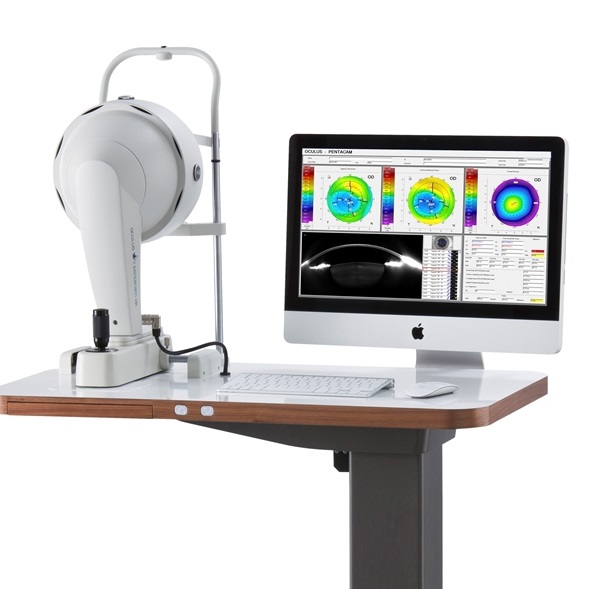

3차원 각막 단층 촬영 장비

독일 OCULUS 社 PENTACAM HR

• 초고해상도 샤임플러그 카메라가 약 2초 동안 360도 회전하며 각막 모양의

모든 정보를 촬영하고, 각막 모양(고위 수차 High Order Aderration)과 난시

의 정도, 동공 크기 등을 정확히 파악

• 전방의 깊이, 백내장이 진행된 정도에 대한 정보를 제공